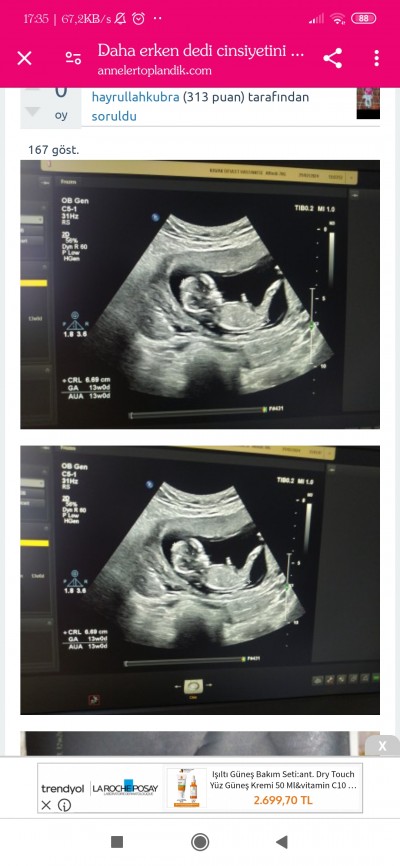

Kızlar ultrasondan cinsiyet anlayan var mı nub teorisi mi ne varmıs bakabilir misiniz

Tipi biraz erkek gibi geldi ama Allah gönlündekini hakkında hayırlı eylesin

Sırt üstü yatıyor yandan sadece bacağı gözüküyor nerden tahmin edelim kız :D

Nub teorisine göre bakıyorlar ya o yuzden sordum

İcime erkek dogdu ama.

Erkek bence canim

Erkek gibi geldi bana

Şu bacagın ustundeki nub işte o yukar kalkık ya erkek diyorlar ama saglıklı olsunda ınsallah kızdır ya

Hayırlısı olsun doktor erkege benziyor net değilim 1 ay sonra bakalım dedi ama ınsallah kızdır saglıklı olsun tabş ama bir oğlum var ınnsan kız ıstıyor

Erkek hissettim Rabbım gönlündekini versin